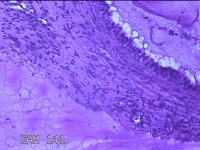

宫颈2点、3点、9点组织

性别

女

年龄

38岁

临床诊断

人乳头瘤病毒感染

一般病史

宫颈其他HPV12阳性

标本名称

大体所见

1.“宫颈2点组织”:灰白粉红色组织0.8x0.5x0.2cm一块。 2.“宫颈3点组织”:灰白粉红色组织0.7x0.5x0.2cm一块。 3.“宫颈9点组织”:灰白粉红色组织0.7x0.5x0.2cm一块。

图3